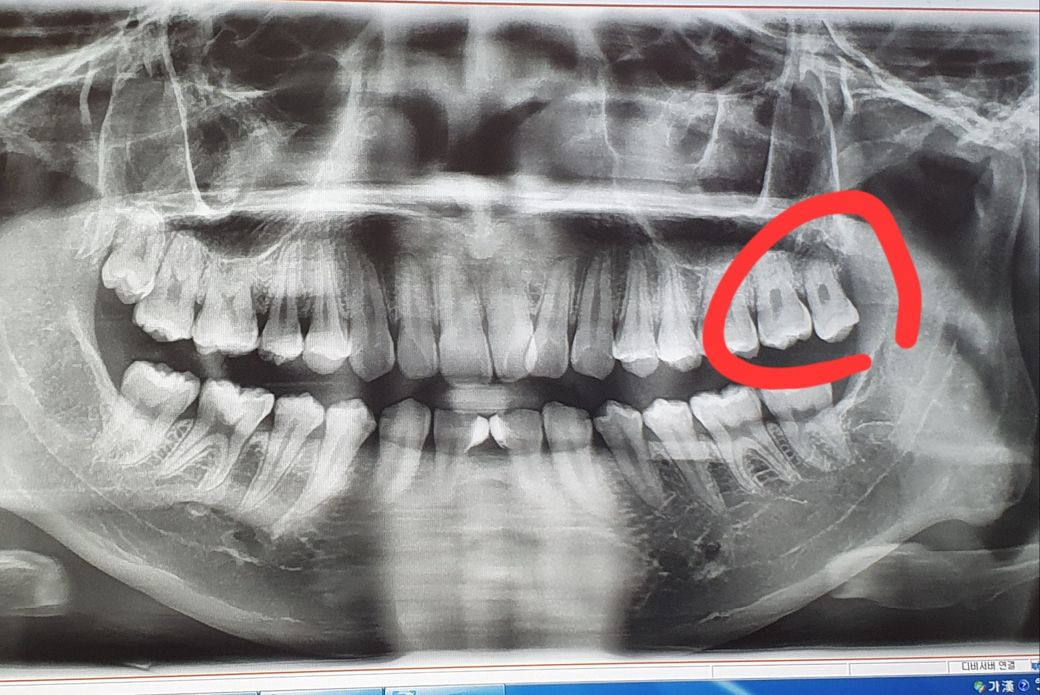

처음에 치과에서 위쪽 사랑니도 다 빼는게 좋다해서

먼저 불편한 사진 왼쪽에 ? 위쪽 사랑니는 음식물이 끼고 잇몸안에 좀 묻혀있어서

제가 동그라미 친게 제 오른쪽 치아인지 모르겠는데

저기는 나름 다 나와있는거 같은데 혹시 이런 경우에 마취 안하고 뽑는 경우도 있나요?